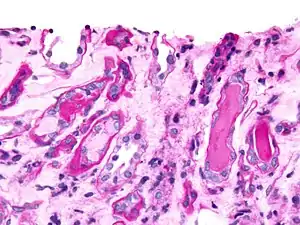

Epithelial cell casts

This cast is formed by inclusion or adhesion of desquamated epithelial cells of the tubule lining. Cells can adhere in random order or in sheets and are distinguished by large, round nuclei and a lower amount of cytoplasm. These can be seen in acute tubular necrosis and toxic ingestion, such as from mercury, diethylene glycol, or salicylate. In each case, clumps or sheets of cells may slough off simultaneously, depending on the focality of injury. Cytomegalovirus and viral hepatitis are organisms that can cause epithelial cell death as well.